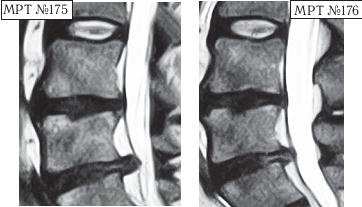

На МРТ № 168 наблюдается состояние поясничного отдела позвоночника: секвестрированная грыжа межпозвонкового диска в сегменте LIV-LV с разрывом задней продольной связки, отрывом фрагмента секвестра с его дорсальной миграцией, абсолютный стеноз спинномозгового канала. Такое состояние — последствия лечения протрузии межпозвонкового диска с применением хиропрактической техники манипуляций на позвоночнике (мануальная терапия). На МРТ № 169 — состояние поясничного отдела позвоночника после лечения методом вертеброревитологии: отсутствие грыжи межпозвонкового диска в сегменте LIV-LV, отсутствие стеноза спинномозгового канала. Разные люди, разные случаи. В следующем примере столь значительное ухудшение состояния здоровья пациента было спровоцировано его индивидуальными занятиями на приспособлении для вытяжения позвоночника. А всё началось с банального желания избавиться от «стартовых» болей в пояснице. ![]() На МРТ № 170 наблюдается состояние поясничного отдела позвоночника: ретроспондилолистез LV (соскальзывание позвонка относительно другого позвонка), протрузии межпозвонковых дисков в сегментах LII—LIV и LIV-LV На МРТ № 171 наблюдается состояние поясничного отдела позвоночника: ретроспондилолистез LV увеличение протрузии межпозвонкового диска в сегменте LIII-LIV, образование секвестрированной грыжи межпозвонкового диска в сегменте LIV-LV с разрывом задней продольной связки, абсолютный стеноз на этом уровне. На МРТ № 172 — состояние поясничного отдела позвоночника в середине первого курса лечения методом вертеброревитологии (после двух недель от начала лечения): наблюдается положительная динамика, выраженная ретрузия секвестра грыжи межпозвонкового диска в сегменте LIV-LV, визуально прослеживается увеличение высоты межпозвонкового диска в том же сегменте, что свидетельствует о начавшемся активном процессе его восстановления, значительное уменьшение стеноза спинномозгового канала на данном уровне. «Стартовые» боли в пояснице в основном проявлялись, когда данный человек выходил из автомобиля. В течение нескольких минут они ему «мешали распрямить спину». Потом, правда, исчезали и могли вновь напомнить о себе после длительного сидения в кресле или в автомобиле. Но так как пациент в силу своих служебных обязанностей вынужден много сидеть (проводить многочасовые совещания, работать с бумагами и так далее), то, естественно, эти боли его раздражали. Как говорится, чрезмерная бюрократия вредна не только для здоровой экономики страны, но и для здоровья самого бюрократа. После того как ему сделали снимок (МРТ № 170) и выяснили, что данные боли возникают вследствие развития спондилолистеза, то, естественно, пациенту предложили операцию с целью стабилизации поражённого сегмента. Не поверив нашим эскулапам (нет пророка в своём Отечестве), пациент отправился в знаменитую клинику за границу, где «светилы» зарубежной медицины (в основном наши бывшие соотечественники) также подтвердили необходимость в оперативном разрешении данной ситуации. Однако пациент, хотя досконально и не разбирался в вопросах заболеваний позвоночника, но зато умел делать выводы из чужих ошибок. Менее двух лет назад его коллега после операции на позвоночнике (кстати, в той же зарубежной клинике) променял солидную должность и кресло «большого начальника» на инвалидность, поэтому этот человек оперироваться не стал и решил пойти другим путём. Приехав домой, он начитался различной рекламы по лечению остеохондроза и его осложнений и выбрал для себя наиболее удобный способ лечения, который вполне устраивал его в режиме служебной деятельности. Обратившись в специализированный медицинский центр по лечению остеохондроза, он приобрёл там специальное приспособление для вытяжения позвоночника и получил от специалистов данного центра комплекс упражнений на нём. Месяц добросовестных тренировок, совмещённых с вытяжением позвоночника (согласно рекомендациям специалистов!) дал свои закономерные результаты. «Стартовые» боли в пояснице при подъёме, из-за которых и началась вся эта история, пациента уже не волновали, поскольку он вообще перестал не только сидеть, но даже ходить. Естественно, начались и другие проблемы в позвоночнике. Следующий месяц в стационаре неврологии (в хирургию упорно не хотел) дали положительные результаты: острые боли постепенно утихали от воздействия сильных обезболивающих препаратов. Пациент смог вставать на ноги, с посторонней помощью проходить от пяти до десяти метров. Сделали снимок (МРТ № 171), на котором выявили секвестрированную грыжу межпозвонкового диска в сегменте LIV—LV с разрывом задней продольной связки. До этого времени ему не могли провести обследования из-за некупируемых болей, а от наркоза он отказывался. Врачи диагностического центра, проводившие МРТ-обследование, посоветовали ему обратиться ко мне. В этот же день, когда больного привезли ко мне на приём, я взялся за эту работу. Через две недели лечения методом вертеброревитологии данный пациент смог самостоятельно приезжать на автомобиле (за рулём). По своей инициативе он сразу сделал ещё одно МРТ (результат интересный, МРТ № 172), на котором можно наблюдать процесс обратного движения грыжи, то есть когда фрагменты выпавшего межпозвонкового диска «заходят» обратно в межпозвонковый диск. Другими словами — процесс ретрузии секвестра грыжи межпозвонкового диска в сегменте LIV-LV а также активный процесс восстановления самого диска. ![]() На МРТ № 173 (увеличенный фрагмент МРТ,№ 171) наблюдается секвестрированная грыжа межпозвонкового диска в сегменте LIV-LV с разрывом задней продольной связки, абсолютный стеноз на этом уровне. На МРТ № 174 (увеличенный фрагмент МРТ № 172) наблюдается состояние межпозвонкового диска в середине первого курса лечения методом вертеброревитологии (после двух недель от начала лечения): положительная динамика, выраженная ретрузия секвестра грыжи межпозвонкового диска в сегменте LIV-LV Вот ещё одни снимки МРТ другого пациента, которые наглядно демонстрируют процесс ретрузии грыжи диска. ![]() На МРТ № 175 наблюдается состояние поясничного отдела позвоночника: компенсированная протрузия, грыжа Шморля в сегменте LIV-LV, спондилёз, гипертрофия задней и передней продольных связок, грыжа межпозвонкового диска сегменте LV—SI, стеноз спинномозгового канала. |